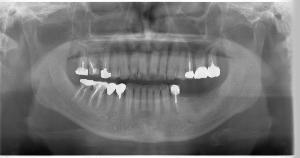

- レントゲン撮影

- 必要に応じてCT撮影(後日)

CTデータを用いて、コンピューター上で精密なシミュレーションを行います。